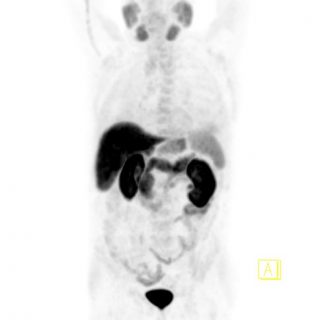

PET Scan à la Fluorocholine

Bilan d’extension et de rechute d’un adénocarcinome prostatique.